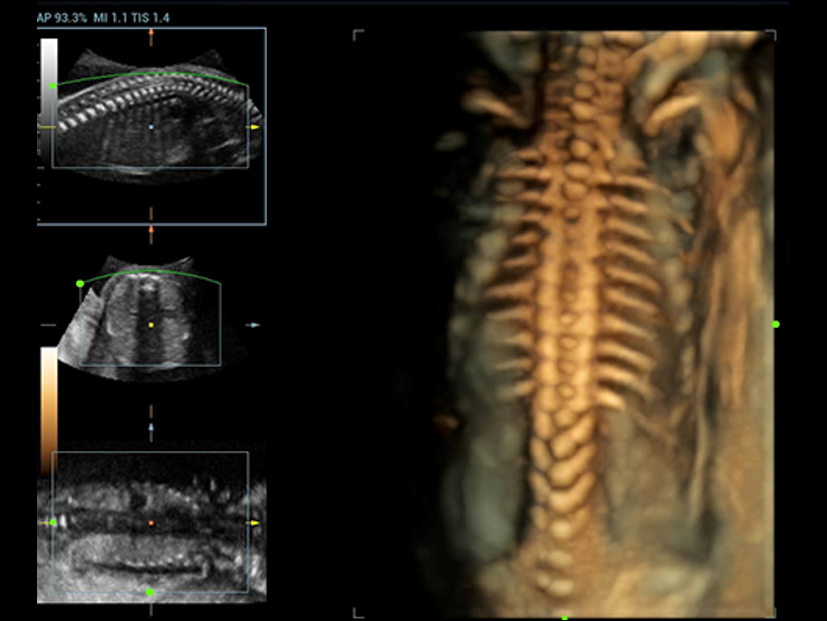

Fin dalla sua fondazione Mindray esplora continuamente nuovi modi per migliorare l'affidabilit├Ā diagnostica. Equipaggiata con la pi├╣ rivoluzionaria tecnologia ZONE Sonography?, la nuova piattaforma ZST+ di Resona 7 porta la qualit├Ā dell'immagine ecografica ad un livello superiore con l'acquisizione per zone e l'elaborazione dei dati canale.

Oltre alla qualit├Ā delle immagini di livello eccellente, Resona 7 migliora anche le capacit├Ā di ricerca clinica il rivoluzionario V Flow per la valutazione emodinamica vascolare, e l'acquisizione piani pi├╣ intelligente dal set di dati 3D per la diagnosi del sistema nervoso centrale fetale. Combinando il pi├╣ intuitivo funzionamento multi-touch basato su gesti e tutte le caratteristiche cliniche essenziali, Resona 7 sta veramente portando nuove tendenze nellŌĆÖinnovazione dellŌĆÖecografia.